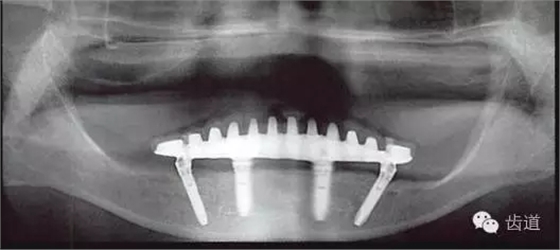

本例種植修復(fù)的問題

咬合平面前高后低

與上頜弓有垂直向?qū)ξ魂P(guān)系的,僅有雙側(cè)第一磨牙